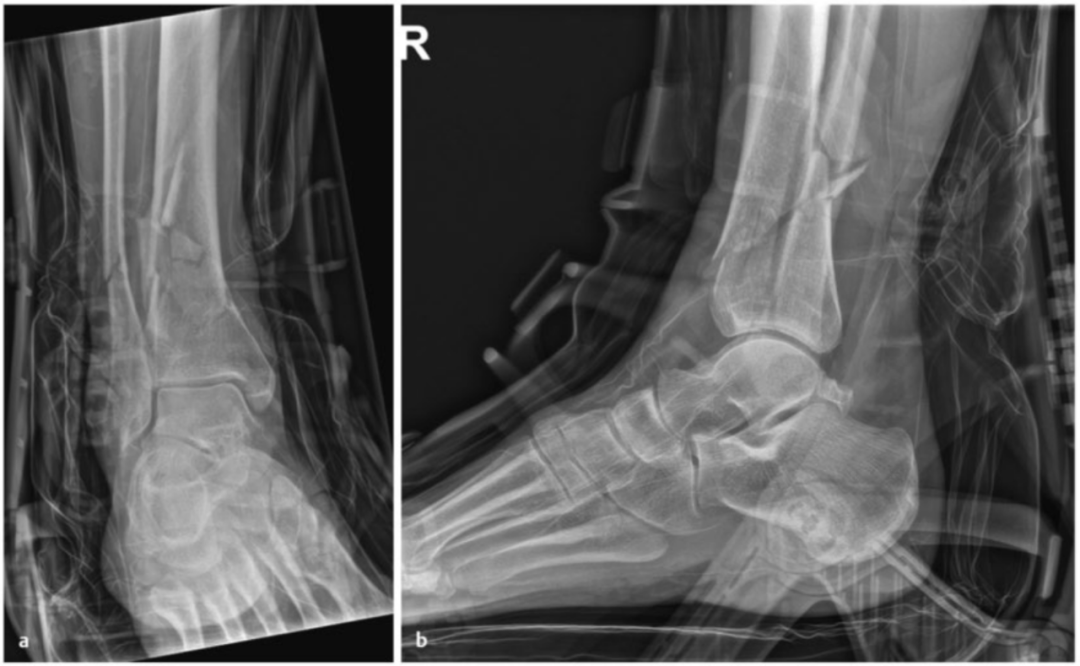

典型病例 1

病例1在受伤后送往医院急诊,首先进行了跨踝关节外固定架。尽管患者初始存在Ⅱ度闭合性软组织损伤,但由于及时进行了复位并植入外固定架,未需实施筋膜间室切开术。在术前CT图像中,可清晰观察到3个主要骨折块及1个中央粉碎区。通过及时植入外固定架,可恢复关节位置,并有效避免软组织损伤进一步加重。

待软组织状况改善(出现 “皮肤皱纹征”)后,开始对患者进行手术治疗,首先处理腓骨(遵循 “先处理腓骨” 原则)。术中检查发现韧带联合存在不稳定情况。

术中三维CT 扫描确认骨折达到解剖复位,内植物位置良好。术后影像学检查证实骨折解剖复位,内植物位置正常。患者术后恢复过程顺利,关节功能恢复良好。